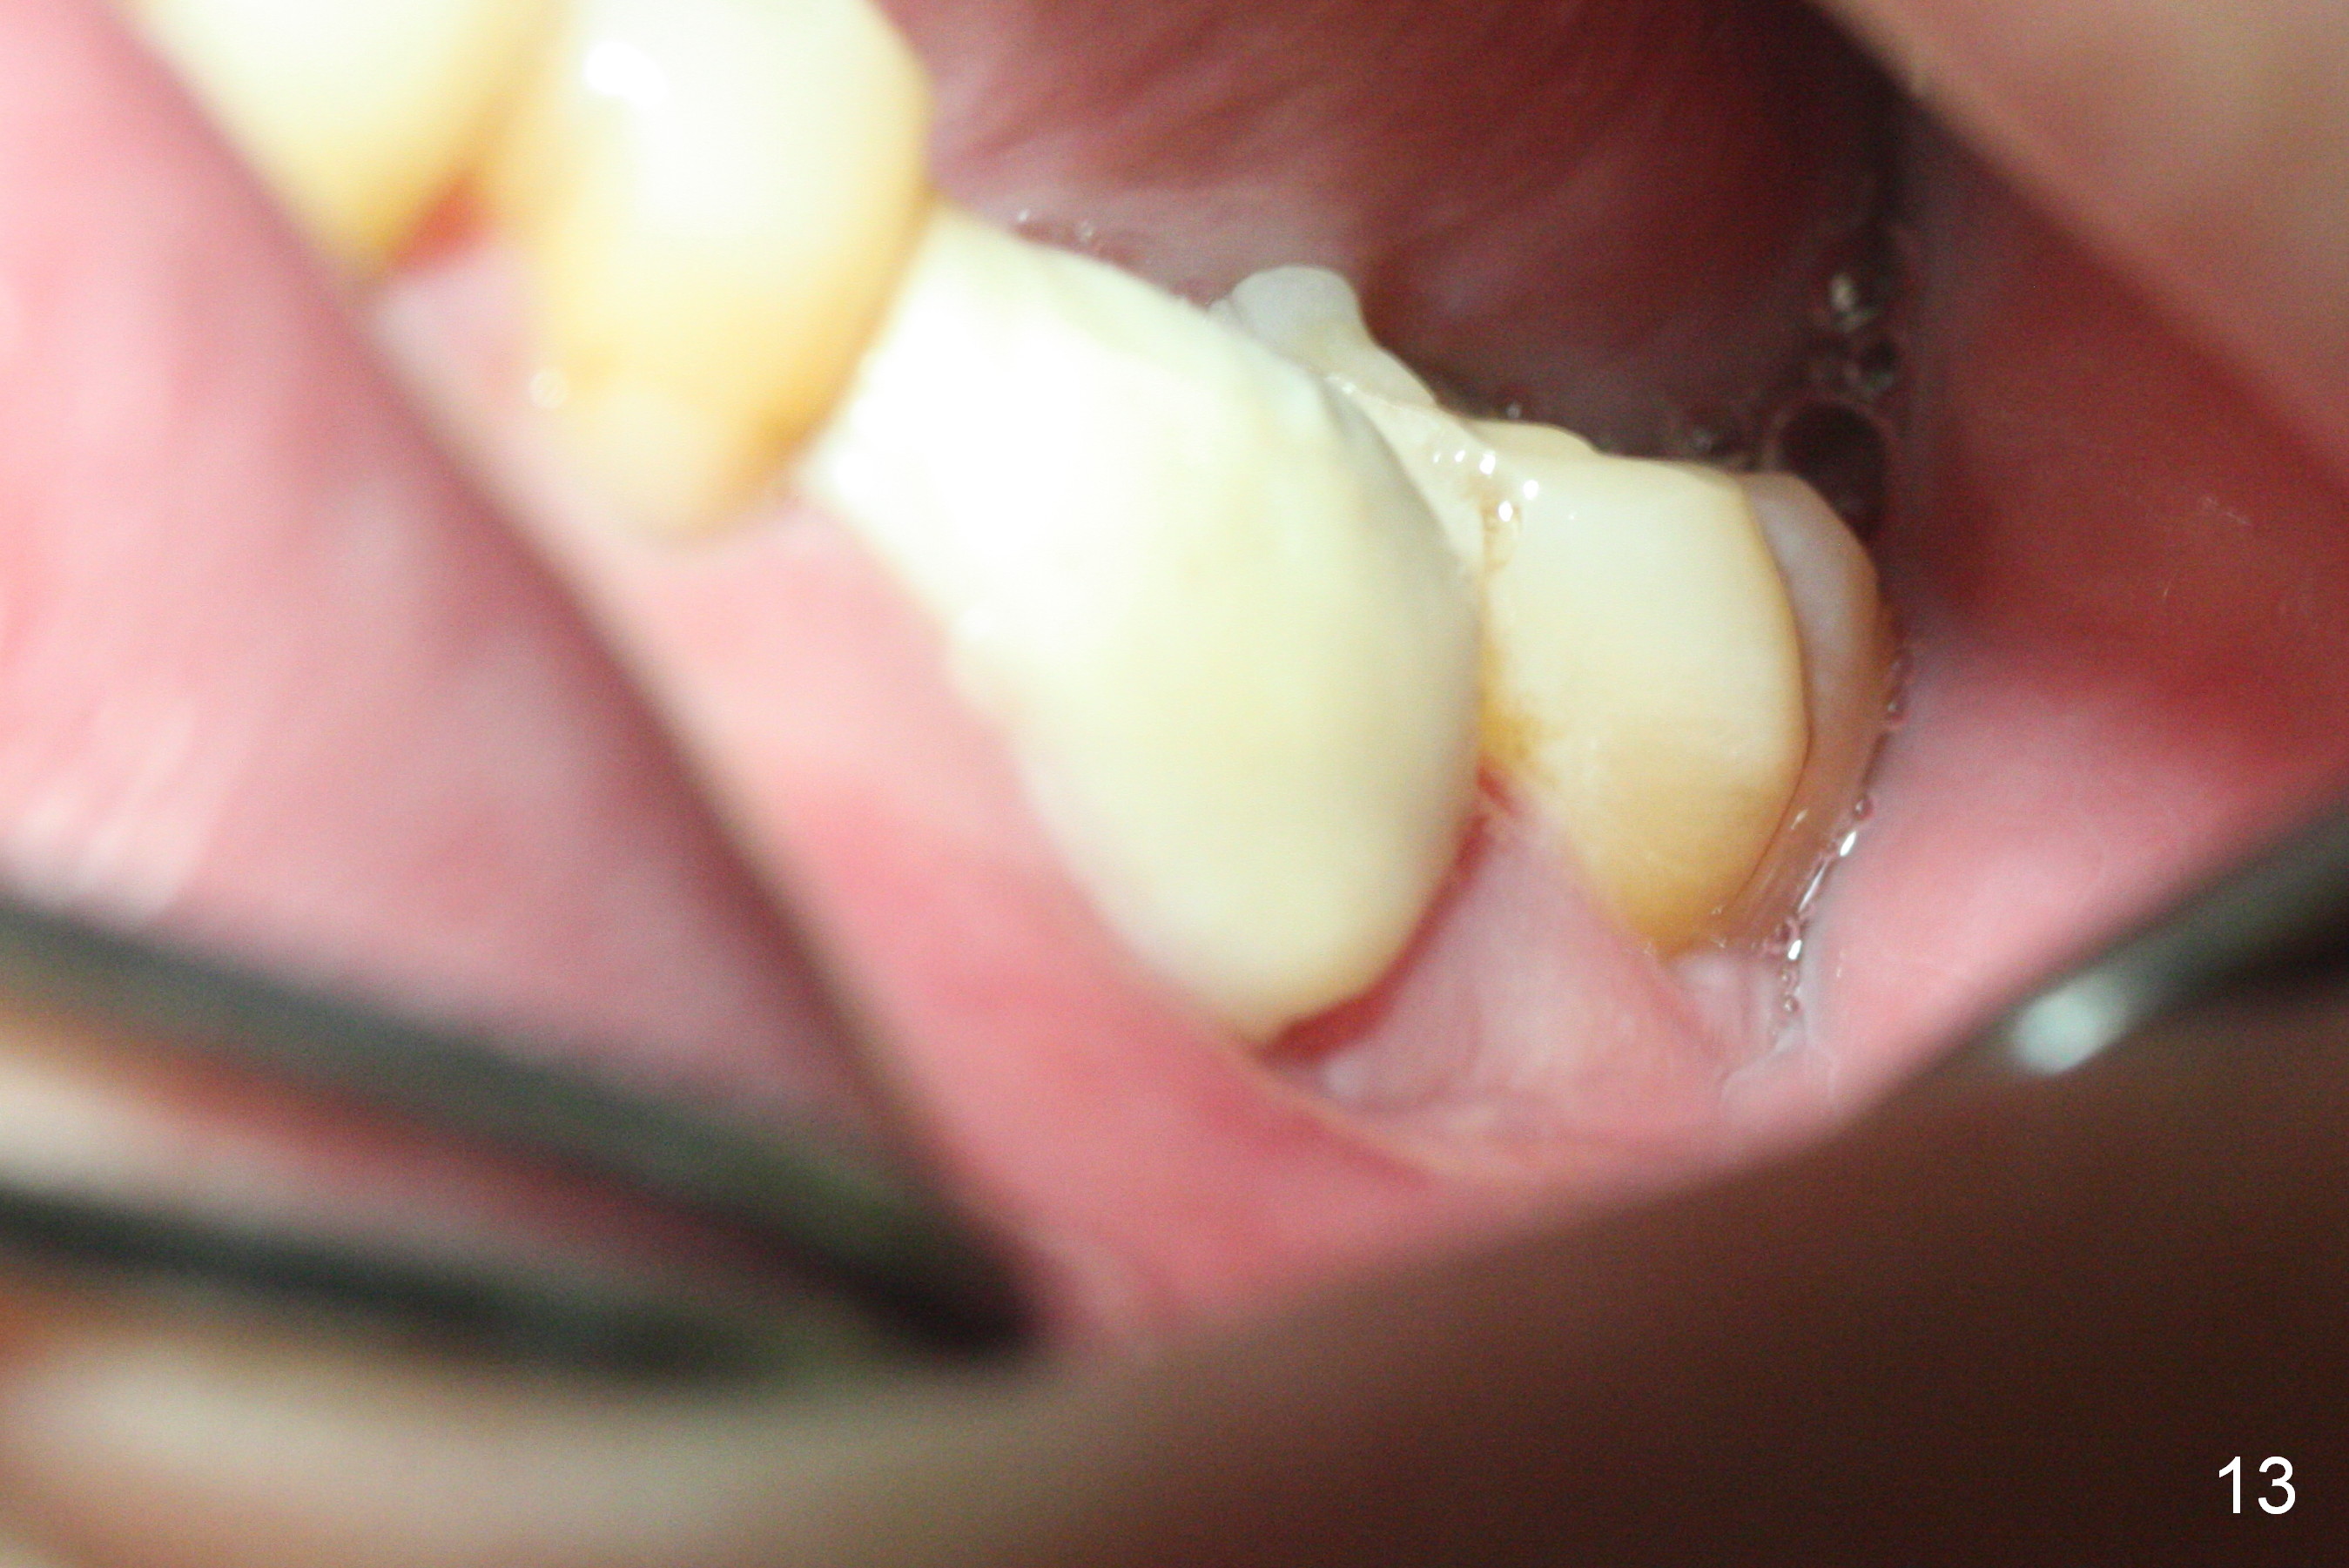

After Chlorhexidine irrigation, a piece of Osteogen plug is inserted (Fig.12), followed by closure of the wound with a new layer of acrylic (Fig.13).